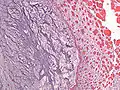

Micrograph of an atrial myxoma. H&E stain.